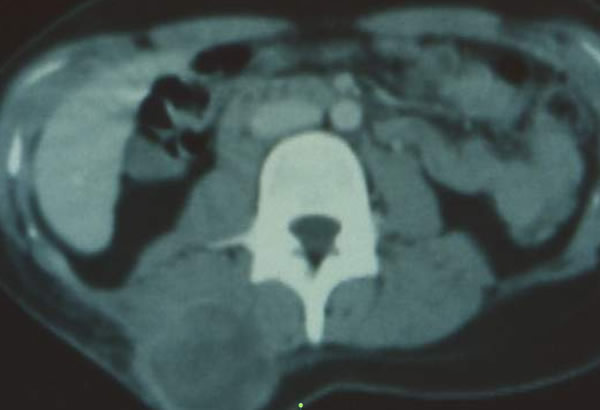

Liposarcome lombaire

Liposarcome de la loge antérieure de cuisse

Liposarcome de la loge postérieure de cuisse

Liposarcome du creux poplité

La coexistence d'aspects de "lipome inhomogène" et de zones avec une densité cellulaire (30) doit faire porter le diagnostic de liposarcome.